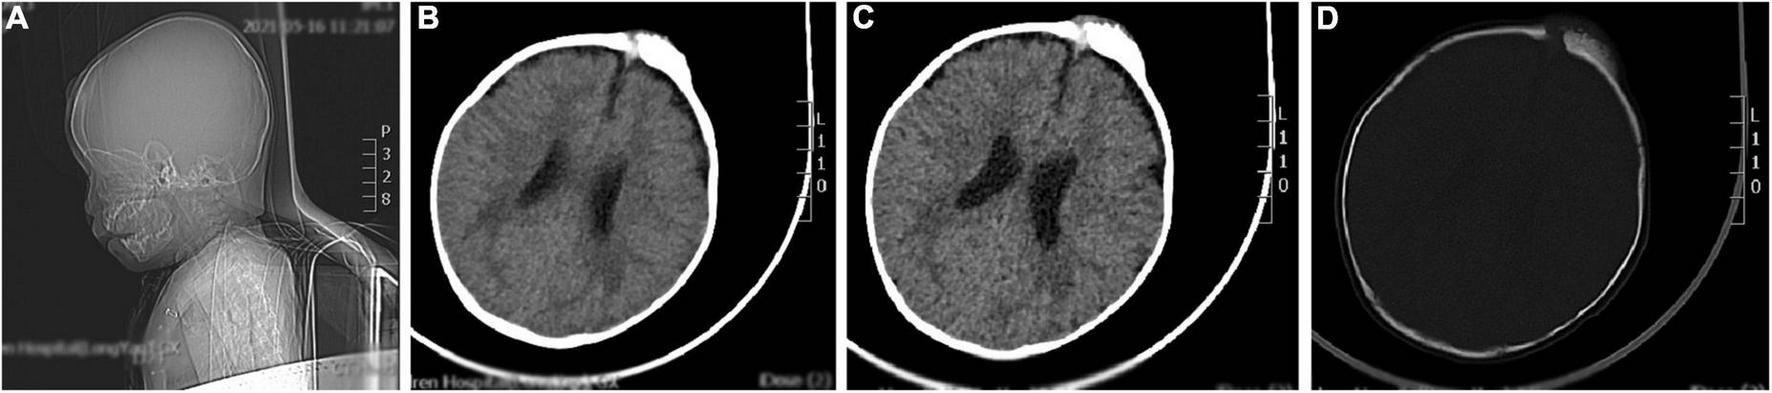

Brain computed tomography scan details

The brain CT scan showed irregular bone structure with mixed density mass on the left side of the cranial plate in the forehead, slightly reduced brain mass density in the bilateral parietal lobes, and wider ventricles and extracerebral spaces as shown in Figure 1.

FIGURE 1

A representative image of the head CT scan shows the irregular bone structure with mixed density mass on the left side of the cranial plate in the median frontal area, slightly reduced density in the bilateral parietal lobes, widening of the ventricles and extracerebral space, and thickening of the septal sinus mucosa. (A) Sagittal view shows a mass in the frontal area. (B,C) Soft tissue window at the central level of the lateral ventricle show a high-density mass in the left frontal region. (D) Bone window at the central level of the lateral ventricle: the bony structure of the left cranial plate in the middle frontal region is irregular, and there is a mixed density mass shadow.